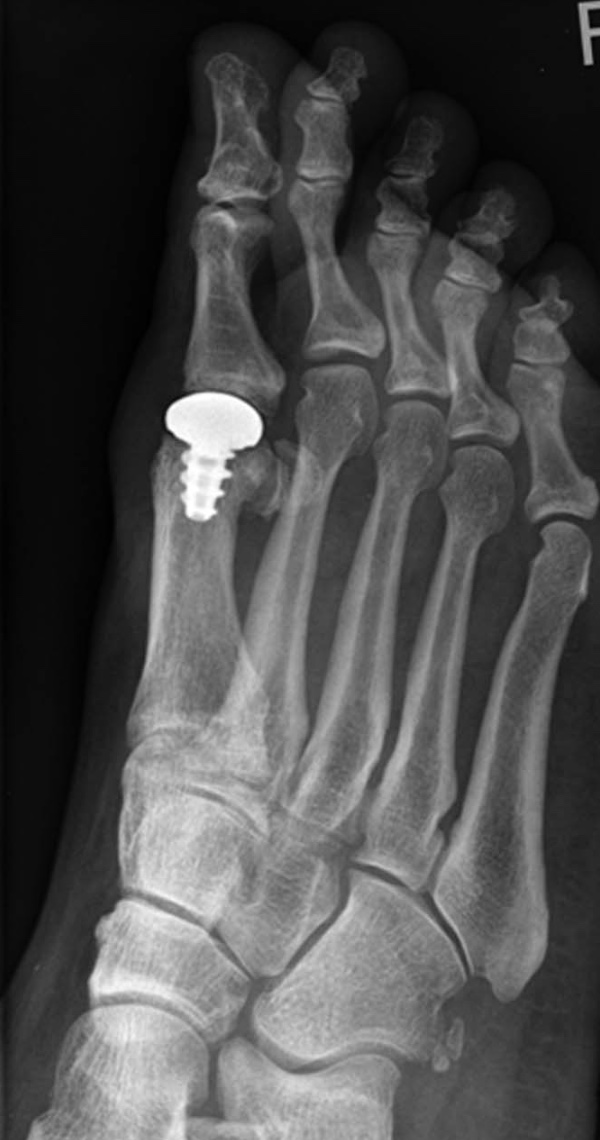

From ar.inspiredpencil.com

Hallux Rigidus X Ray Foot Hallux Rigidus Hallux rigidus is a type of arthritis affecting the big toe's metatarsophalangeal (mtp) joint where the big toe meets the foot. It is one of the most. Hallux rigidus is a common foot condition characterized by pain and loss of motion of the 1st mtp joint in adults due to degenerative. It’s a type of degenerative arthritis that. Hallux rigidus. Foot Hallux Rigidus.